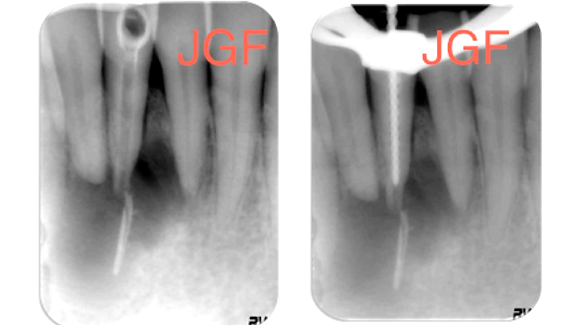

Radiográficamente (Fig. 1) se observó una amplia sombra radiolúcida que se extendía desde la pieza #42 hasta la 31, desplazando la misma. Además, se observó una radiopacidad alargada en el centro de la lesión periapical compatible con un cono de gutapercha de grueso calibre. A nivel apical falta de continuidad del ápice compatible con ensanchamiento exagerado (posible perforación apical) unida a reabsorción apical por el tamaño de la patología.

Durante el tratamiento, después de la toma de conductometría, desinfección, conformación y la confirmación de una sobrepreparación del foramen (Figs. 2 y 3) realizado en la primera sesión, se procedió a una segunda cita. Después de observar la completa ausencia de la fístula vestibular, se intentó colocar el tapón de MTA (Proroot, Maillefer) en apical, que se extruyó (Fig. 4) debido a la extremada divergencia del ápice y posible presión realizada durante su colocación. Se realizó un segundo intento, el cual tuvo éxito y se dejó completar su endurecimiento por 24 horas para proceder a la colocación de gutapercha termoplastificada en una tercera cita (Figs. 5 y 6) y dejar espacio para poste para la restauración. Se le remitió al rehabilitador para que le realizara un blanqueamiento interno (Fig. 7) y procediera a su restauración inmediata para evitar contaminación o filtración. Se realizaron controles radiográficos anuales (Fig. 8 a 12) debido a la motivación del paciente.

En las radiografías de control se observó cambios de contraste en la patología periapical existente, así como en la radiopacidad de la punta de gutapercha extruída; también ausencia de signos clínicos de la patología.